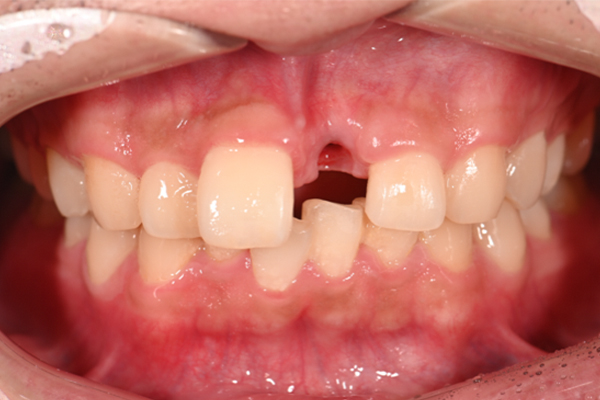

| 主訴 | 奥歯で噛めない、顎が痛い |

|---|---|

| 治療内容 | 奥歯のインプラント治療、前歯・奥歯の被せ物治療 |

| 治療期間 | 6ヶ月 |

| 治療費 | 350万円 |

| 治療リスク | 被せ物をつけた初期の段階で歯がしみることがある(時間とともに改善する) インプラント治療後に3日程度痛みと腫れを伴うことがある |